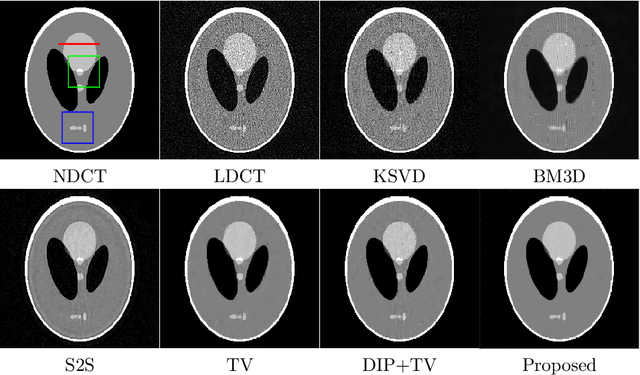

Abstract:Low-dose CT (LDCT) imaging attracted a considerable interest for the reduction of the object's exposure to X-ray radiation. In recent years, supervised deep learning has been extensively studied for LDCT image reconstruction, which trains a network over a dataset containing many pairs of normal-dose and low-dose images. However, the challenge on collecting many such pairs in the clinical setup limits the application of such supervised-learning-based methods for LDCT image reconstruction in practice. Aiming at addressing the challenges raised by the collection of training dataset, this paper proposed a unsupervised deep learning method for LDCT image reconstruction, which does not require any external training data. The proposed method is built on a re-parametrization technique for Bayesian inference via deep network with random weights, combined with additional total variational (TV) regularization. The experiments show that the proposed method noticeably outperforms existing dataset-free image reconstruction methods on the test data.